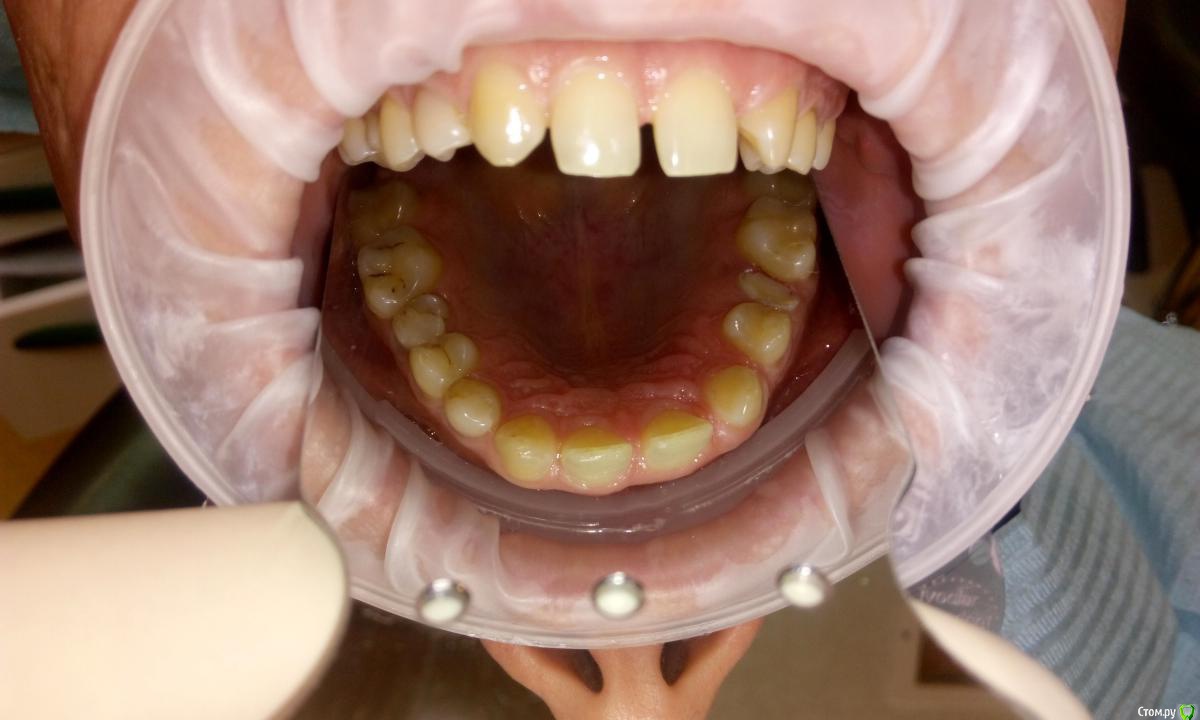

Витторио Орлионе Опубликовано 1 апреля, 2016 Поделиться Опубликовано 1 апреля, 2016 Обратился пациент с желанием красивой улыбки. Из анамнеза стало известно, что боковые резцы были удалены весьма и весьма давно, всё лихо сдвинулось и теперь, господа, мне интересно ваше мнение. Как вернуть парню былую красоту, какие планы лечения можно предложить? Ссылка на комментарий

Карен Аванесов Опубликовано 1 апреля, 2016 Поделиться Опубликовано 1 апреля, 2016 Смотря на что готов пациент. Если просто и быстро, заточить клыки и резцы, но предварительно воск согласовать, более же изощренно, удалить премоляры, затем брекеты и на десерт 2 имплантата. Ссылка на комментарий

Ronin Опубликовано 1 апреля, 2016 Поделиться Опубликовано 1 апреля, 2016 воск, виниры до 4, и коронки на пятые, или ортодонт и тоже самое, или ортодонт и импл, зависит от бюджета, времени и ожиданий Ссылка на комментарий

ccenter3751 Опубликовано 2 апреля, 2016 Поделиться Опубликовано 2 апреля, 2016 Перед удалением пересчитайте зубы здесь молочный клык Панорам снимок оцените премоляры и к ортодонту за местом для 2 и чуть расширенной дугой Ссылка на комментарий